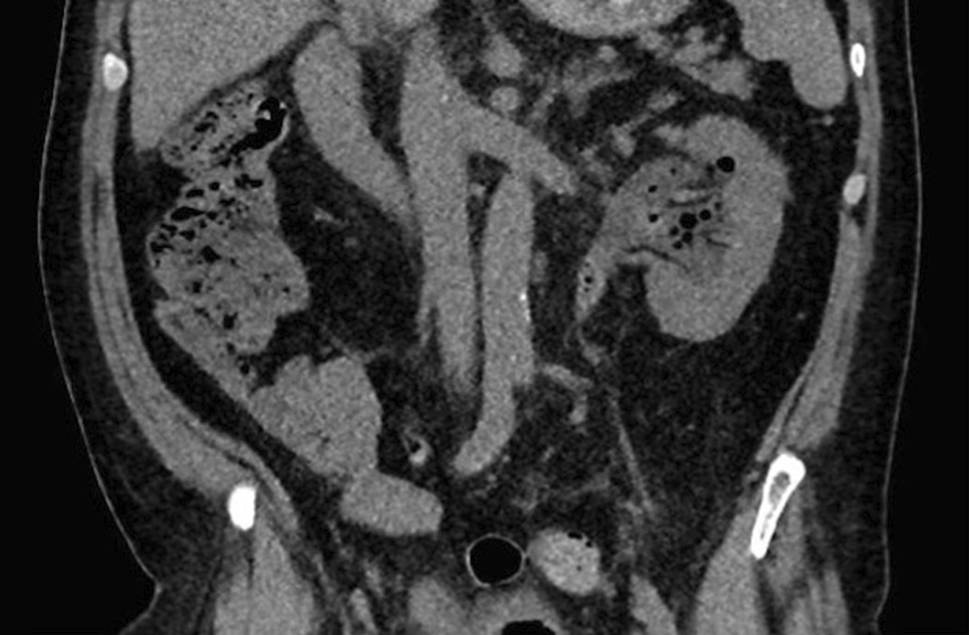

Een 68-jarige man presenteerde zich op de spoedeisende hulp (SEH) met hypotensie e causa ignota. Hij heeft een voorgeschiedenis van een percutane coronaire interventie, cholecystectomie en benigne prostaathyperplasie (BPH) met chronische residuen, waarvoor zelfkatheterisatie. Anamnestisch had hij onderbuikspijn links. Bij aankomst van de ambulance bleek hij hypotensief (60/44 mm Hg) met een polsfrequentie van 70/min zonder koorts. Vervolgens is gestart met vochttoediening en perifere noradrenaline. Op een CT-abdomen zonder excretiefase (fig. 1) werd hydronefrose links gezien, met een massa in het pyelum met luchtconfiguratie. Vanwege aanhoudende hypotensie ondanks adequate vulling werd de patiënt opgenomen op de ICU en werd gestart met antibiotica in de vorm van cefuroxim en gentamicine. Er werd een nefrostomiekatheter (NSK) links en een transurethrale katheter (TUC) geplaatst voor maximale drainage.

Figuur 1

CT-abdomen zonder excretiefase bij aankomst op de SEH: hydronefrose links met een intrapyelische massa met luchtconfiguratie. Differentiële diagnose: fungal ball, lithiasis of tumor